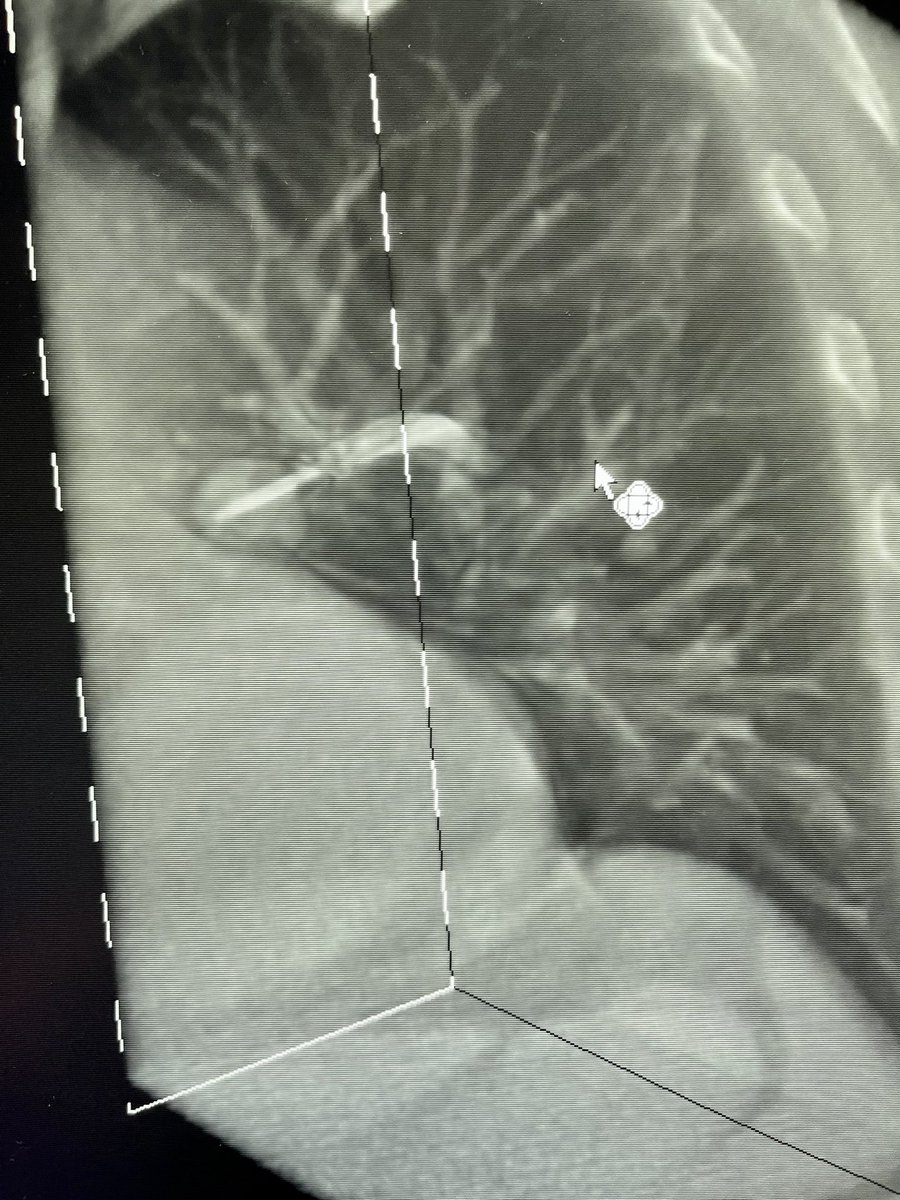

Bhadra & Condra CBCT Bronchoscopy

If you don't like the road you are on, pave a new one: Cone Beam CT Bronchoscopy.